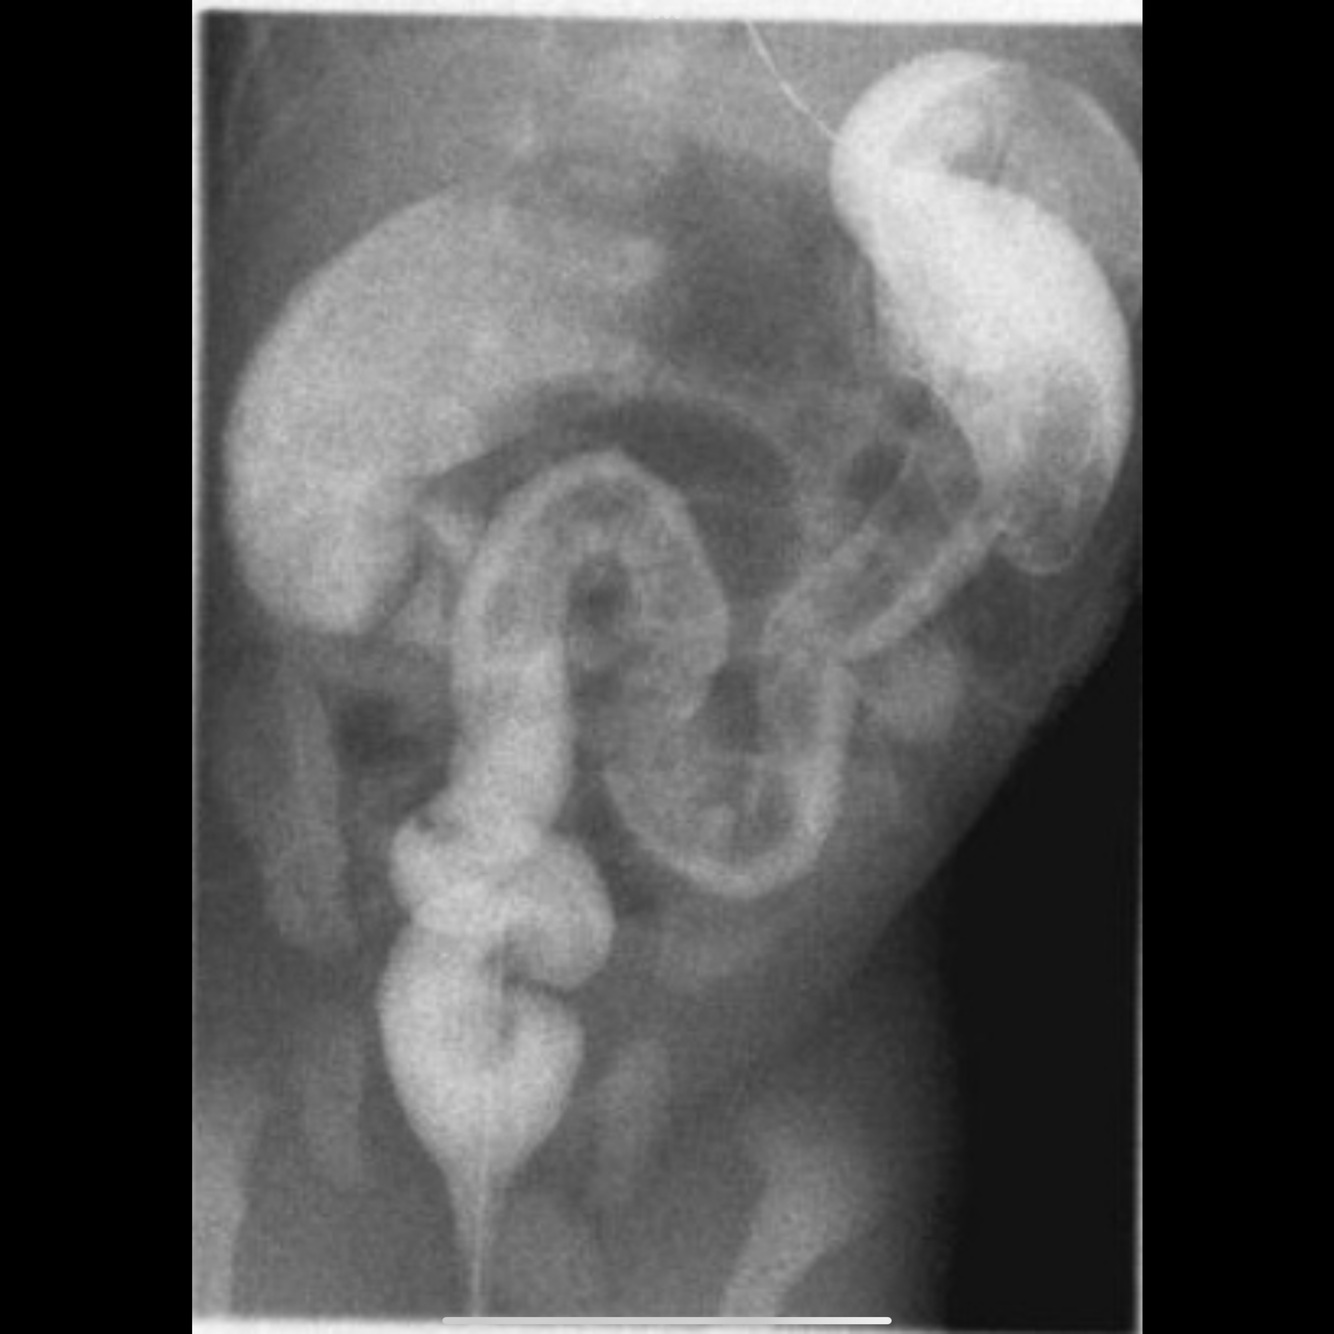

Hirschsprung disease: On barium enema study, she has proximal colonic dilatation